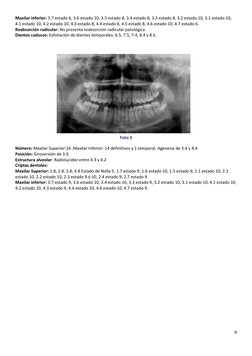

Foto 3 Nmero: Maxilar Superior:16 .Maxilar Inferior: 14 definitivos y 1 temporal. Agenesia de 3.4 y 4.4 Posicin: Giroversin de 3.3. Estructura alveolar: Radiolucidez entre 4.3 y 4.2 Criptas dentales: Maxilar Superior: 1.8, 2.8, 3.8, 4.8 Estado de Nolla 5. 1.7 estado 9, 1.6 estado 10, 1.5 estado 9, 1.1 estado 10, 2.1 estado 10, 2.2 estado 10, 2.3 estado 9 10, 2.4 estado 9, 2.7 estado 9 Maxilar inferior: 3.7 estado 9, 3.6 estado 10, 3.4 estado 10, 3.3 estado 9, 3.2 estado 10, 3.1 estado 10, 4.1 estado 10, 4.2 estado 10, 4.3 estado 9, 4.4 estado 10, 4.6 estado 10, 4.7 estado 9.